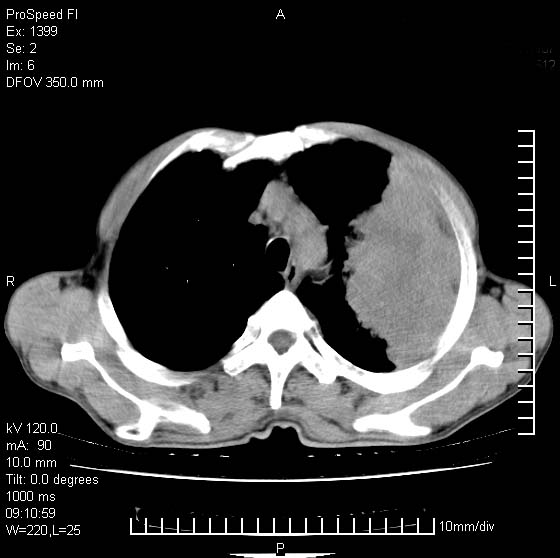

以下是引用卜一在2007-1-19 9:55:00的发言:[br]左肺沿胸膜下巨大肿块影,边缘呈分叶征,纵隔内见肿大淋巴结,右肺内另见一不规则结节影 .考虑:左肺周围性肺癌伴纵隔 右肺内转移.